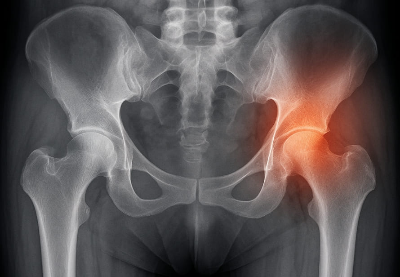

고관절은 대퇴골(허벅지뼈)과 골반이 연결되는 관절로, 신체 하중을 지탱하고 대부분의 움직임을 관여하는 중요한 부위입니다. 공 모양의 대퇴골두와 그를 감싸는 비구라는 구조가 만나 회전과 굴곡이 자유롭습니다. 고관절통증은 이 부위의 이상으로 인해 발생하며, 초기엔 증상이 뚜렷하지 않지만 점점 일상생활에 불편을 줍니다.

③ 고관절염, 대퇴골두무혈성괴사

- 고관절염: 연골이 점점 닳아 없어지는 퇴행성 질환으로, 중장년층에 많습니다. 관절 마모로 인해 고관절통증 증상이 진행됩니다.

- 대퇴골두무혈성괴사: 대퇴골 머리 부분에 혈류가 차단되어 뼈 조직이 괴사하는 질환입니다. 음주, 스테로이드 장기복용, 외상 등이 주된 고관절통증 원인입니다.

- 영상검사: X-ray, MRI, CT 등을 통해 연골 손상이나 구조적 이상 여부 확인